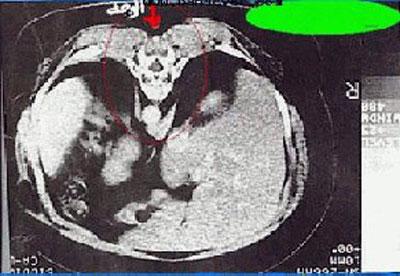

Существует еще одно, не менее жуткое и поражающее явление – антистигмат – изображение дьявола. В 2000-х у одной женщины в Англии во время ультразвукового исследования – в теле нашли изображение дьявола.

Врач была потрясена и шокирована. В итоге было принято решение сделать увеличение фрагмента.